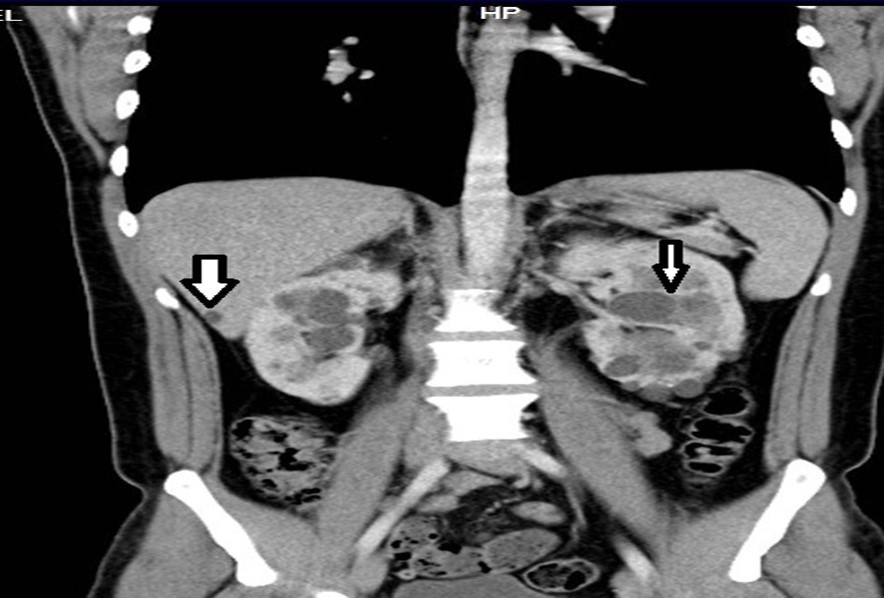

33-year-old male, son of the woman from case 1, with diagnosis of polycystic kidney and liver disease (Figure 3, Figure 4) since 29 years old , with normal liver and kidney function; At that moment general measures were started based on a diet low in sodium, increasing the consumption of natural liquids, avoiding nephrotoxic drugs and monitoring blood pressure.

Figure 3.Contrast CT coronal reconstruction shows small liver cysts, kidneys are enlarged by multiple cysts.